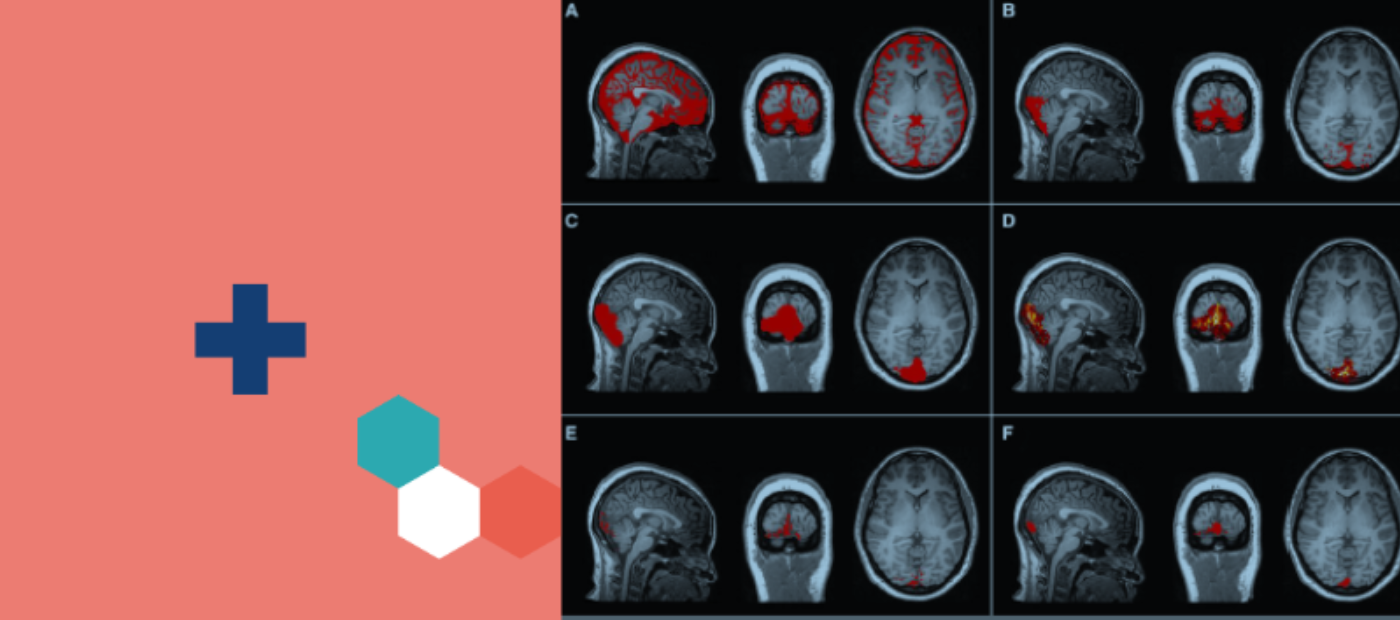

Pictured: Figure 2 – Confluence of sinuses region of interest generation process (see article for more information)

Researchers analysed a dataset of 51 adults with depression, as well as 25 healthy age matched participants that were originally recruited as part of the BIODEP study to investigate the role of inflammatory processes in depression. Each subject provided a blood sample before undergoing a PET scan and MRI during the original data collection. Peripheral inflammatory markers were assessed from blood while inflammatory activity in the anterior cingulate cortex, skull marrow, and dural sinuses was assessed with PET sensitive to immune cell density.

An analysis of the data revealed that the inflammatory activity in dural sinuses and skull marrow, which the researchers identified as a potential reservoir of immune cells, is closely associated with inflammatory activity in both the body and the brain, and this association was present in those with depression and in healthy controls. This association was stronger in the dural sinuses than in the skull marrow.